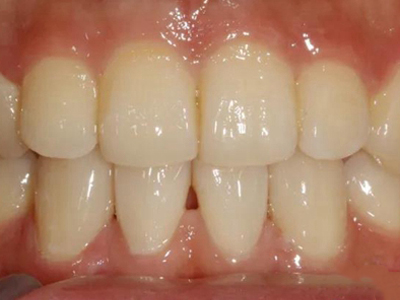

酸蚀症牙齿上有白斑和缺损图

酸蚀症常导致牙齿上呈白垩色改变,即出现像粉笔末样一块块的白色或灰白色斑块,质地松软,会导致牙齿表面不平滑,颜色不均匀,并伴有牙齿缺损的现象。